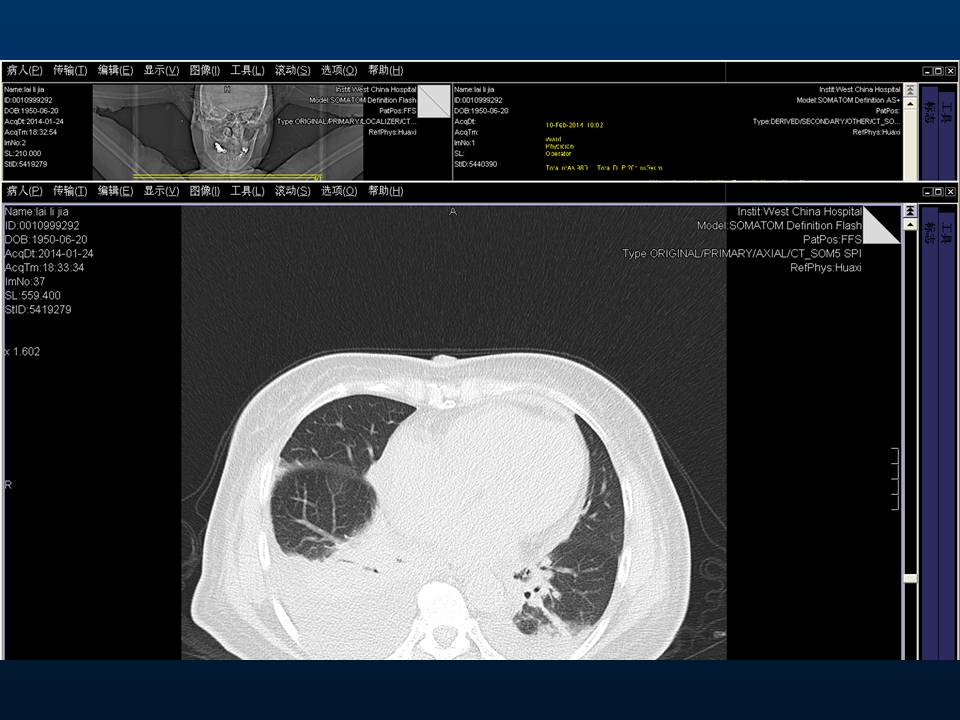

心房颤动(扑动)与“心衰”一例特殊病例报道